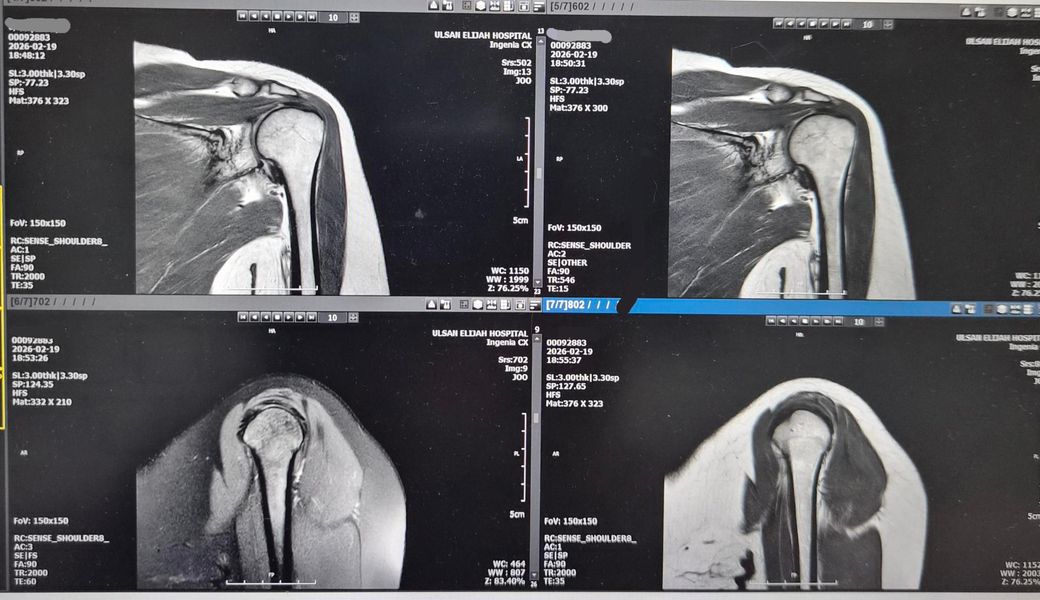

왼쪽어께가 아파서 엑스레이 찍고 MRI저녁에

찍었어요.MRI판독좀 해주세요! 의사소견으로는

골절됬다가 뼈가 붙었다고 했어요. 뼈도좀 튀어나왔죠?그리고

어께충돌증후군이 있다고 치료확인서에 적혀주셨어요. 어께안쪽이 찌릿하고 뭔가 사이에

걸리는 느낌도나요!딱딱 소리도 나구요.

왼쪽어께 통증있어요.앗까는 엑스레이 사진만 올렸었는데 이번에는 MRI같이 올려봐요.

2번사진은 2026년2월19일 사진입니다.

사진만으로 확정 판독은 어렵지만, 말씀처럼 "과거 골절 후 유합되며 뼈 돌출(골극)" 소견이 보이고 견봉 하방이 비교적 뾰족해 보입니다.

두 X-ray를 비교하면 "견봉–상완골 간격이 아주 약간 더 답답해 보일 수는 있으나" 급격히 좁아진 소견은 뚜렷하진 않습니다.

MRI상 "어깨충돌증후군(견봉하 충돌) + 회전근개 자극/염증"이 있어 팔 들 때 걸림·찌릿함·딱딱 소리가 설명됩니다.